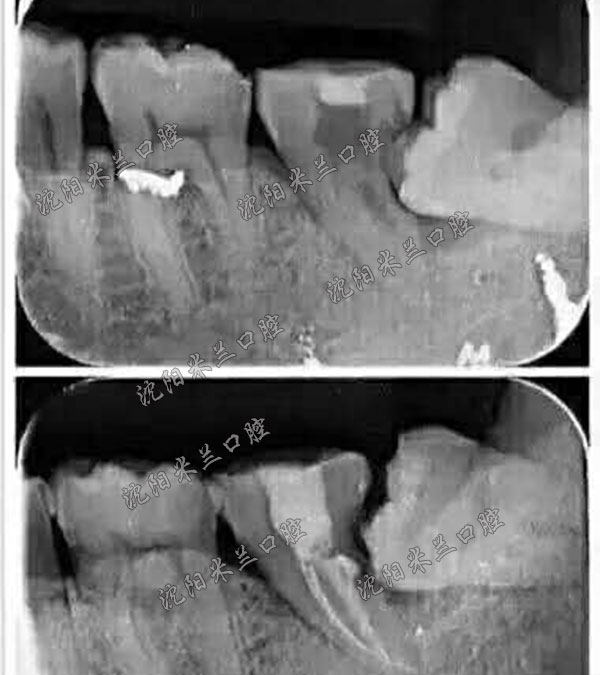

< 牙齿X光片 >